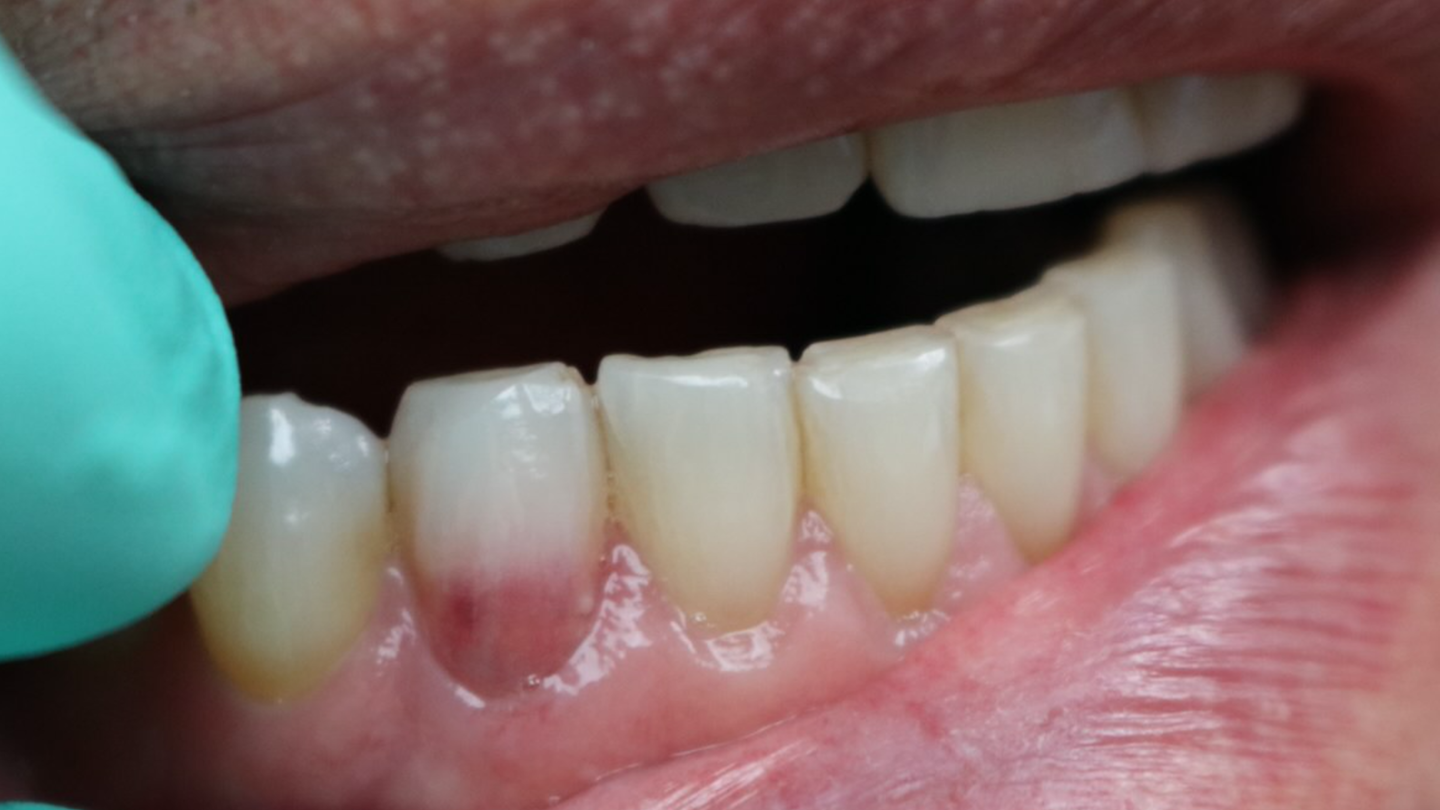

"It looks like I have a pink tooth!" Teeth, Pink What Happens If You Have A Pink Tooth You are looking at lesions that occur either internally or externally due to a resorptive process that results in significant loss of tooth structure. Have you ever noticed a lightly discolored “pink spot” on a tooth and wondered what it was? Find out how to prevent and. Periodontitis is a serious gum infection that damages the soft tissue and bone. What Happens If You Have A Pink Tooth.

Gum disease symptoms and treatment The Implant Experts What Happens If You Have A Pink Tooth Learn how to recognise the symptoms, such as. Have you ever noticed a lightly discolored “pink spot” on a tooth and wondered what it was? Dental resorption is the loss of parts of your tooth due to injury, infection, or other factors. A tooth infection, or dental abscess, can cause severe pain and discomfort, and may spread to other areas. What Happens If You Have A Pink Tooth.